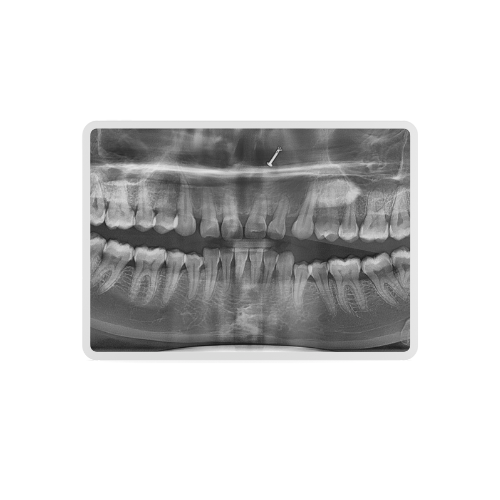

At Kataria Healthcare we are pleased to offer our patients most advanced DIGITAL OPG facility—using the state-of-the-art CBCT system from South Korea by Vatech. It is the first machine in our neighbourhood offering crystal clear DIGITAL OPG images powered through a CBCT system.

A panoramic dental scan (also known as an OPG or orthopantomogram) provides a broad, single-image view of your entire upper and lower jaws, all the teeth, the jaw joints (TMJ) and surrounding bone structures. It is highly valuable for:

- The machine then rotates around your head while capturing a panoramic 2-D image of the jaws and teeth.